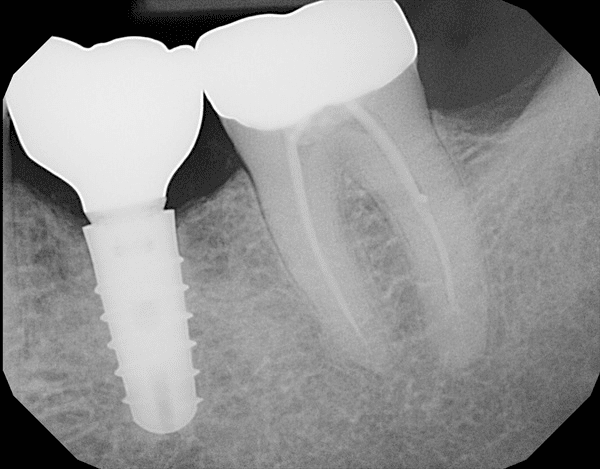

A dental implant next to a root-filled molar toothX-ray of a dental implant in the lower jaw

Let's look at these possible dental implant problems one by one.

First, infection. This can happen in 2 ways. The most common way is that there is already some infection in the jawbone where the implant is going to go.

For example, you may have had an abscess on the tooth, and when the dentist takes the tooth out, the infection is left behind. Normally your own immune system can deal with the infection. Sometimes your dentist will give you antibiotics to help.

But it's possible for some infection remain in the bone. Then, when the implant is put in there, the bacteria that are there interfere with the normal healing process, or "osseo-integration" as Professor Branemark dubbed it.

So the healing process is delayed, while your body tries to fight the residual infection as well as heal the bone around the implant, fusing it to the bone.